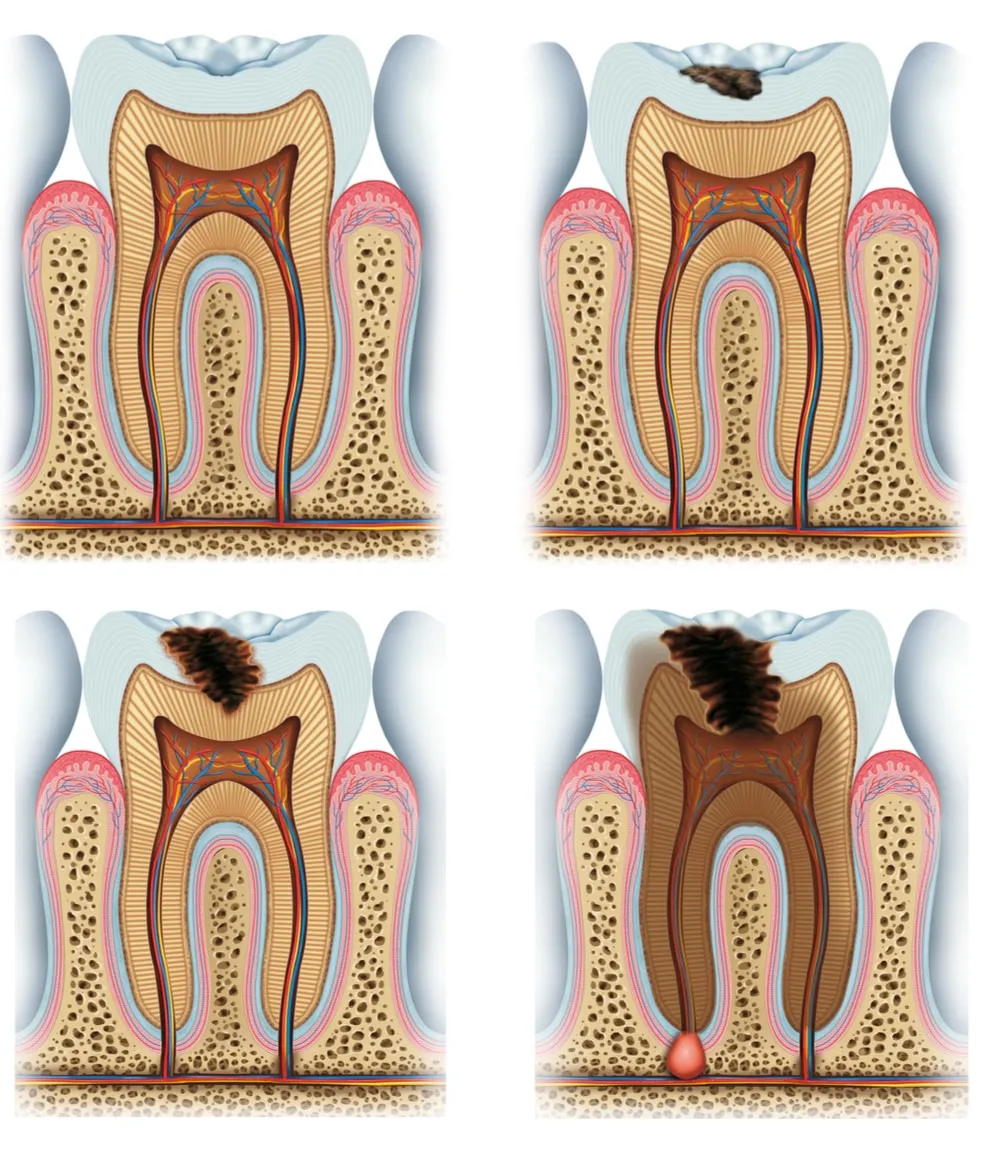

The Role of Enamel

Enamel is the hard, protective outer layer of the tooth. Its primary function is to shield the sensitive inner structures from external stimuli. When enamel is compromised, the underlying dentin, which contains tiny tubules leading to the nerve of the tooth, becomes more exposed. This exposure allows the whitening agents to reach the nerves more easily, resulting in sensitivity.

How Whitening Agents Affect Teeth

Whitening agents work by oxidizing the staining molecules within the enamel and dentin. This process breaks down the stains, making the teeth appear whiter. However, this process can also temporarily dehydrate the tooth, making the enamel more porous. The increased porosity allows the whitening agents to penetrate deeper into the tooth structure and also makes the tooth more susceptible to external stimuli, leading to sensitivity. The duration of the whitening agent’s contact with the tooth and the concentration of the agent play a significant role in the degree of sensitivity experienced. Higher concentrations and longer exposure times can lead to increased sensitivity.